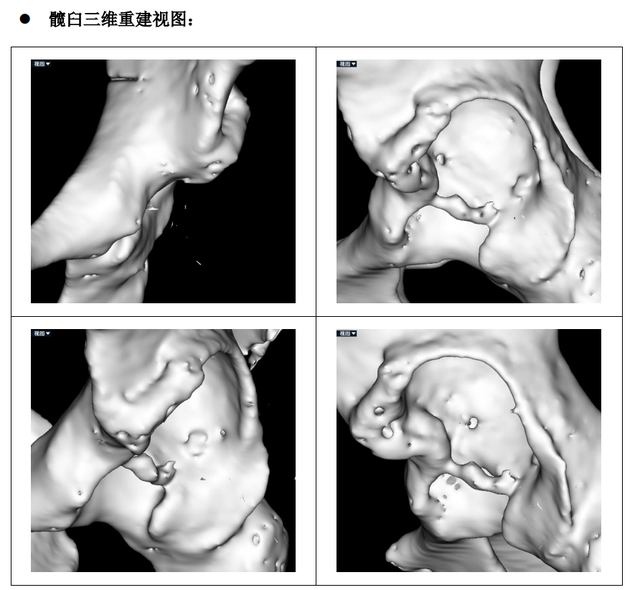

髋臼三维重建图如下:

(术前测量患肢短缩3.3cm,偏距减少4mm)